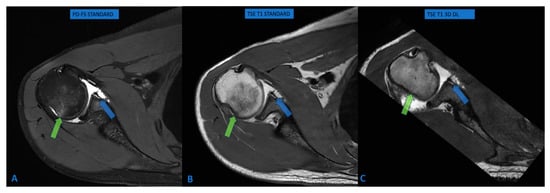

Accuracy of Deep Learning-Driven MR Arthrography of the Shoulder: Compressed 3D in Comparison to Standard FSE Sequences

by Gianluca Tripodi, Flavio Spoto, Giuseppe Ocello, Leonardo Monterubbiano, Paolo Avanzi and Giovanni Foti

Osteology 2026, 6(1), 4; https://doi.org/10.3390/osteology6010004 - 27 Feb 2026

Background/Objectives: Magnetic resonance arthrography is the reference standard for evaluating glenoid labral lesions. Deep learning (DL) reconstruction algorithms may accelerate 3D acquisitions while maintaining image quality. This study assesses the diagnostic accuracy of DL-based isotropic 3D MR imaging for detecting glenoid labral lesions. Methods: This prospective study included 128 consecutive patients (79 men, 49 women; mean age 38.4 years) undergoing shoulder MR arthrography between June 2023 and April 2025. DL-based 3D sequences (acquisition time: 3:26) were compared with conventional multiplanar TSE and PD-FS sequences (acquisition time: 24–28 min). Two independent radiologists assessed glenoid labral lesions, bone marrow edema, and rotator cuff abnormalities using a four-point Likert scale. Sensitivity, specificity, and interobserver agreement were calculated. Results: DL-based 3D sequences demonstrated 94.7–95.1% sensitivity and 100% specificity for glenoid labral lesions, with excellent interobserver agreement (κ = 0.812). The area under the ROC curve was 0.894. Combined 3D protocols (T1 + PD-FS) showed superior accuracy (97.8%) compared to single sequences (90.5%, p = 0.012). For bone marrow edema, sensitivity was 82.9% with 100% specificity. Rotator cuff evaluation achieved 75% sensitivity with 100% specificity. Conclusions: DL-based isotropic 3D sequences provide high diagnostic accuracy for glenoid labral pathology while reducing scan time by 75%. Combined T1 and PD-FS protocols optimize performance. These findings support selective implementation of DL-accelerated 3D protocols in shoulder MR arthrography, particularly for labral assessment, while acknowledging that conventional protocols may remain preferable in specific clinical scenarios. Full article

Show Figures

Figure 1